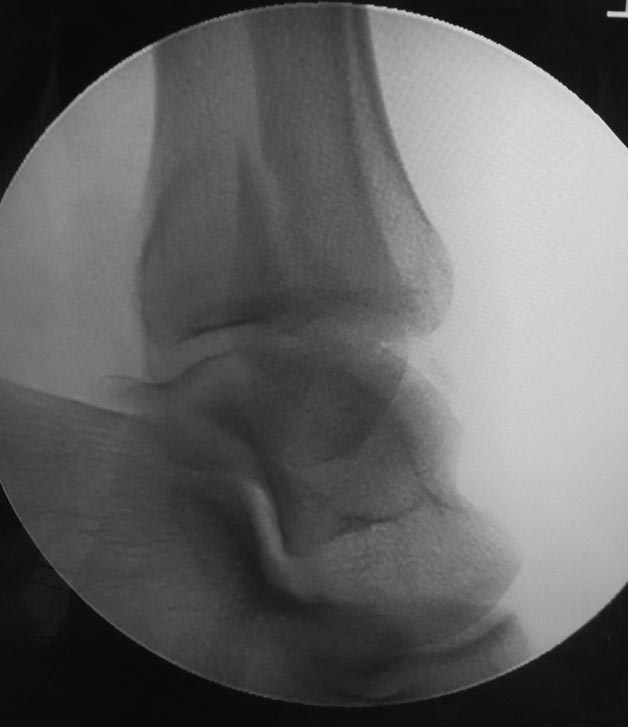

Отправлял до- и послеоперационные снимки, но почему-то проявились только послеоперационные. Досылаю остальные.

На боковом снимке если таран косо стоит, то значит точно трицепс не доразвит(смотрите большеберцо пяточный, тарано-пяточный, большеберцо таранный углы). Недоразвитый ахил тянет пятку это нарушает перекат стопы вот вам и натоптоши